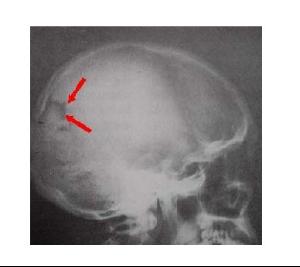

1. 高顱內壓綜合症:顱內壓增高時可導致頭痛、嘔吐,多在活動站立後減輕,久臥後加重。常有眼底視神經乳頭水腫、腰穿腦脊液壓力高於正常。有時頭顱X線或CT可見顱內高壓的特殊改變。